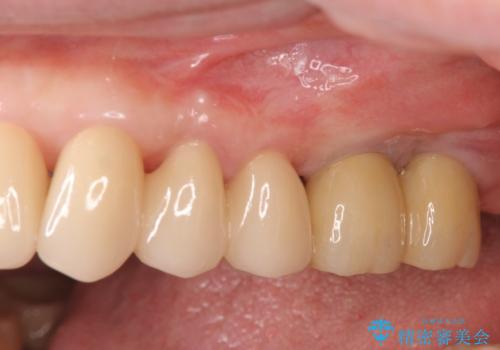

歯周ポケットの徹底的な除去を行なったのち、歯の揺れを抑え、過大な力がかからぬよう連結クラウン(歯周補綴)を行い強大な力に対抗します。

夜間の歯ぎしりにはナイトガードを用いて大きな力がかからないような対処が必要です。